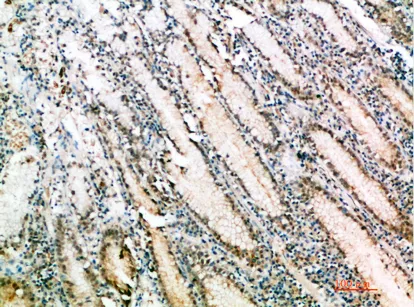

Fhit Rabbit Polyclonal Antibody

Cat: APRab10957